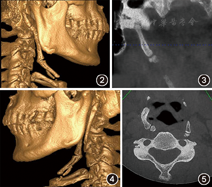

(1)临床资料:患者男性,38岁,因"下颌右侧第一磨牙疼痛2天"于2018年11月14日就诊于郑州大学第一附属医院口腔科门诊。经曲面体层X线片检查,发现下颌骨右侧多生骨两块(图1)。查体:患者一般状况较好,面部对称,双侧下颌角无红肿,无压痛,咽部黏膜正常,无张口受限,颈部活动无受限,右侧颈部下颌骨下方触及长条形硬物,质地坚硬,按压无痛感。患者自述夜间睡眠时张口呼吸,打鼾较重,但无呼吸暂停,无其他自觉症状。锥形束CT(Kavo 3D Exam,美国)检查显示,右侧茎突舌骨韧带可见明显分节的三段骨(图2),第一段骨长21.26 mm,与颞骨下关节窝形成关节(图3),第二段骨长39.79 mm,与第三段骨形成关节,第三段骨长28.16 mm,与舌骨体相距4.78 mm,未见右侧舌骨小角。左侧茎突舌骨韧带可见两段骨(图4),第一段与颞骨相连,是1块长53.74 mm的巨大茎突,第二段骨长12.97 mm,与茎突相距29.33 mm,与左侧舌骨小角相距2.36 mm。患者左侧舌骨大角向内侧弯曲(图5),两舌骨大角游离端内缘之间距离(设为a线)为31.55 mm,舌骨体内缘至a线的距离为28.71 mm,颈椎椎体前缘至a线的距离为3.51 mm。两舌骨大角游离端与第四颈椎之间各有一块直径约4 mm大小的类圆形小骨(图5),左侧小骨距左侧舌骨大角1.46 mm,距第四颈椎体中部外侧缘4.07 mm,右侧小骨距右侧舌骨大角1.00 mm,距第四颈椎右侧横突(横突孔位置)前缘3.75 mm。